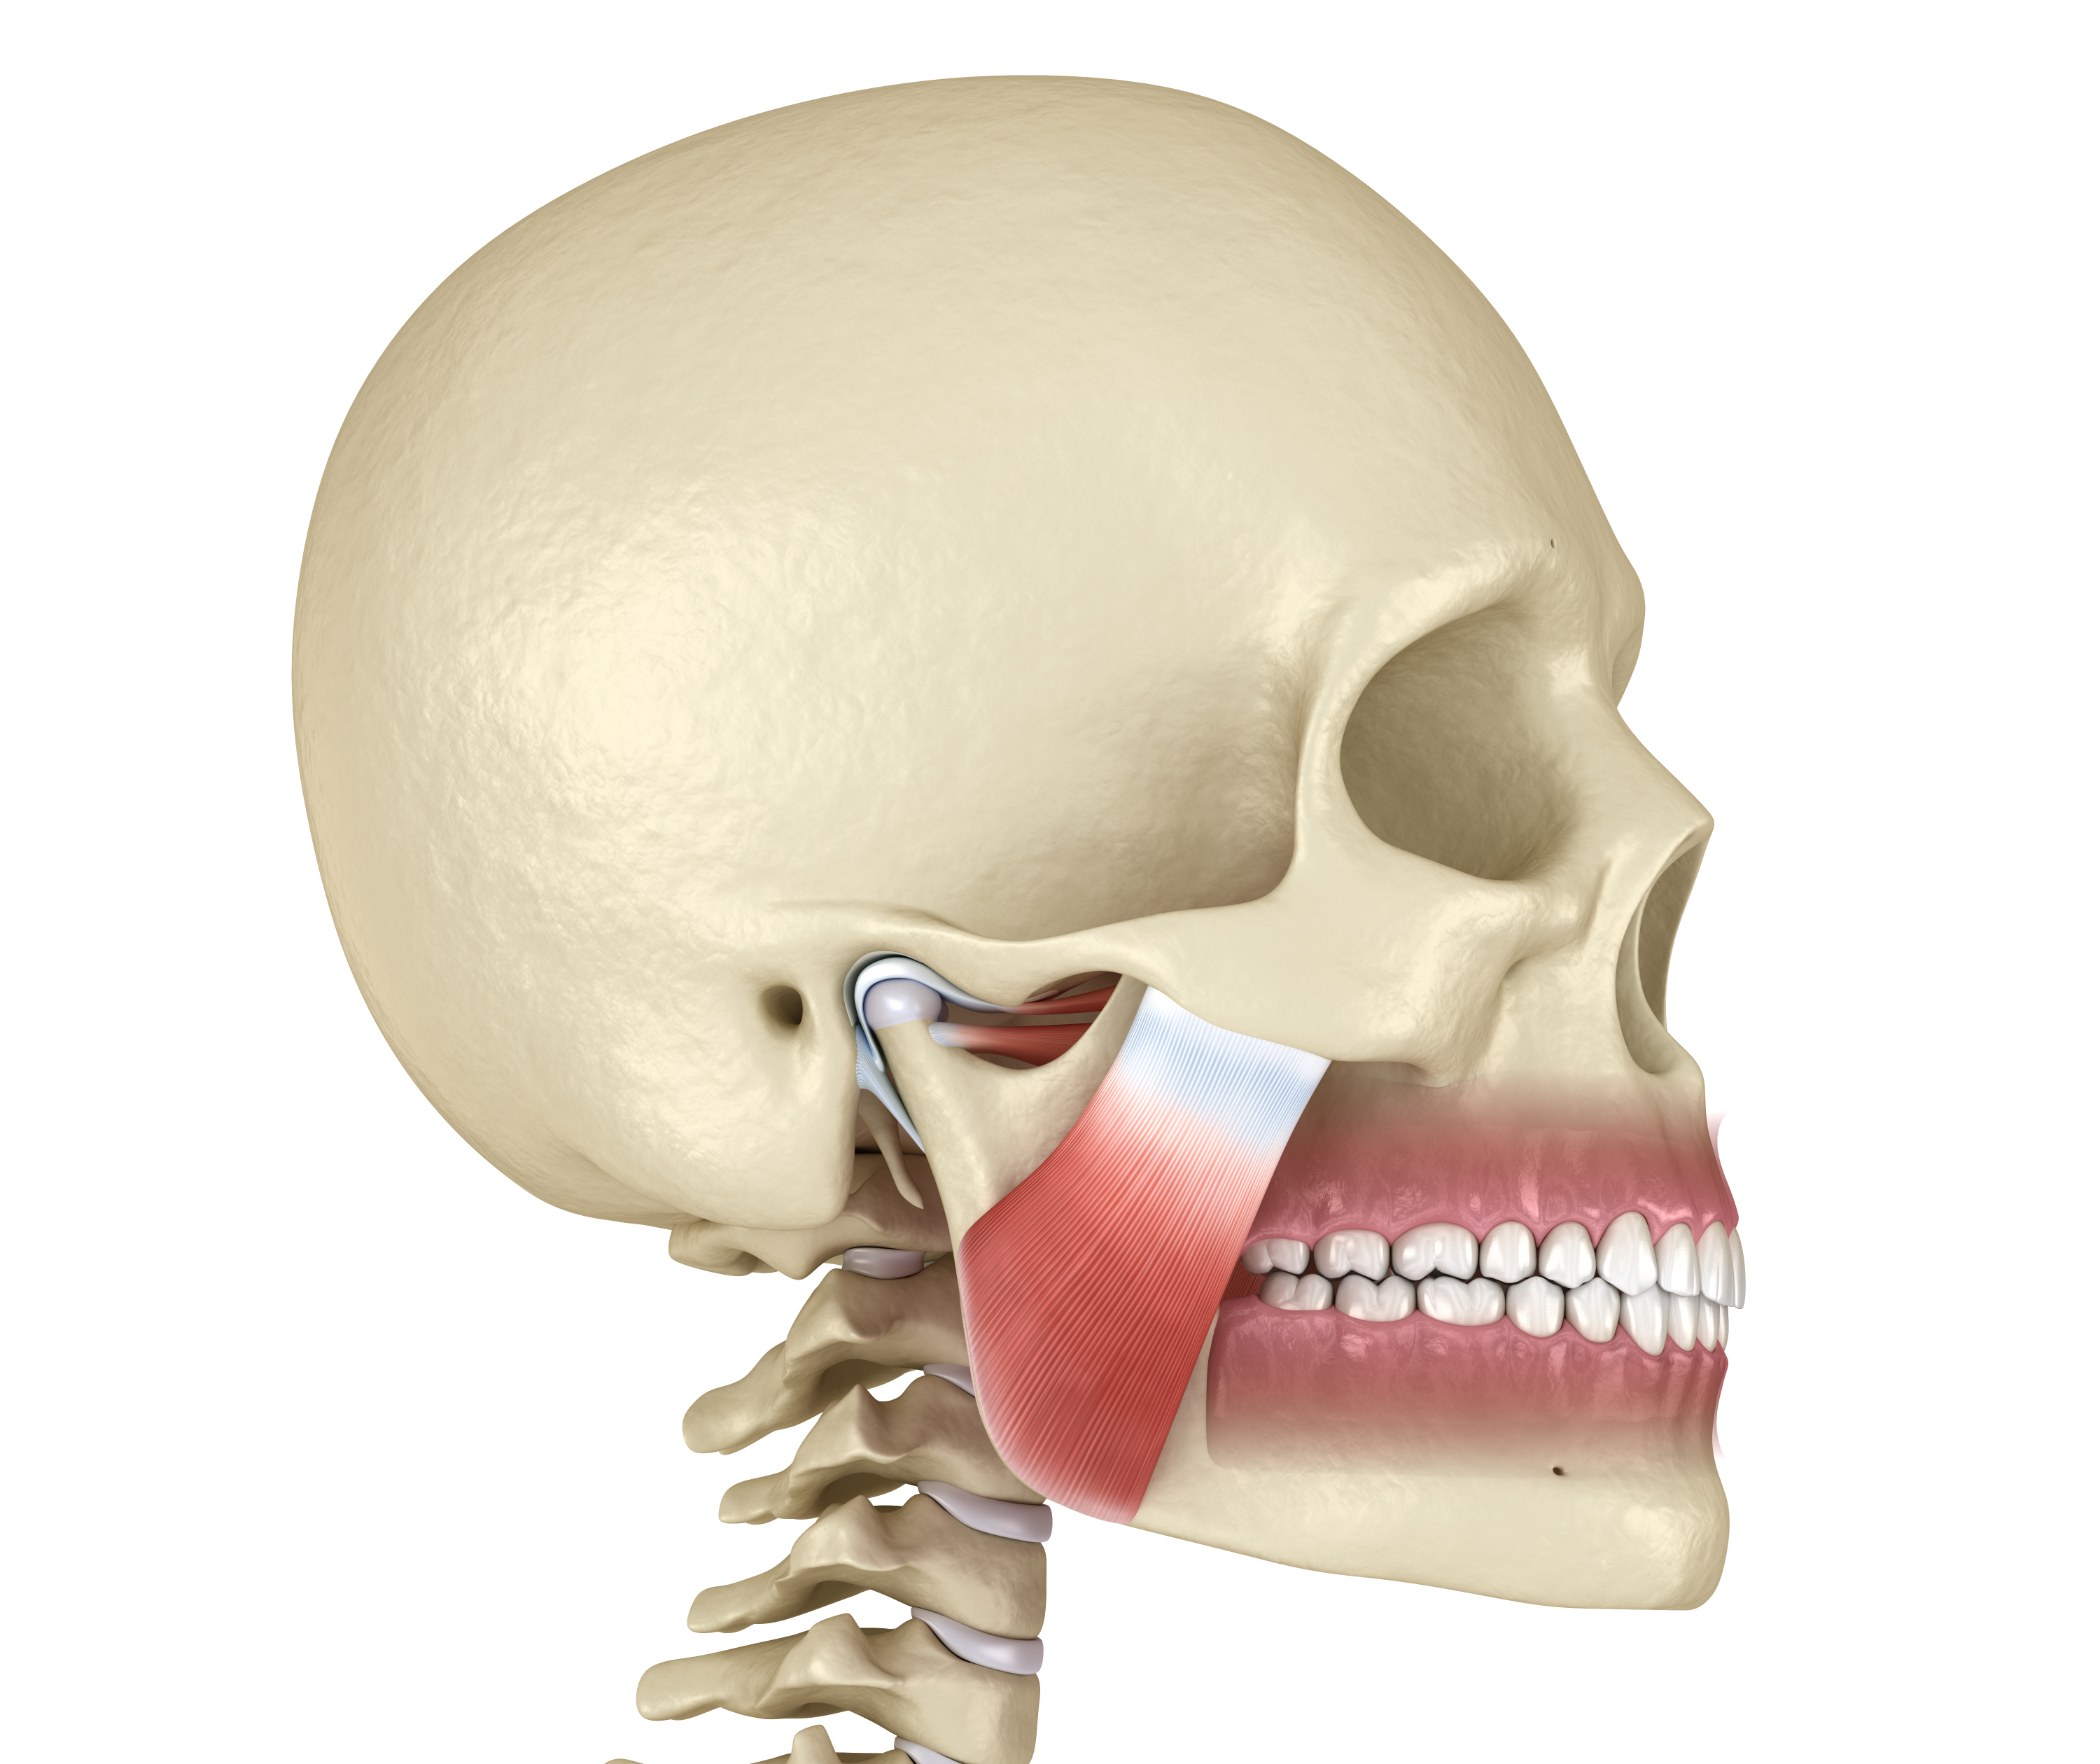

متعددة لكشف العظام ومجموعة من تقنیات الأسلاك أو الطلاء. تعتمد تقنیة إعادة التموضع التي یستخدمھا جراحو الفم والوجھ

والفكین على موقع الكسر وشدتھ. في حالة حدوث كسر في الفك العلوي أو السفلي ، یمكن تثبیت الأقواس المعدنیة على

Traumatic facial injuries are the fractures of the facial bones like mandibles (lower jaw), maxillae (upper jaw), orbits, palates, noses (nasal notch and nasal crest), zygomas (cheekbones), eye sockets, frontal bones and combinations of these bones. These kinds of facial fractures occur due to many factors, such as car and sport-related accidents. These injuries can affect the ability to see, breathe, speak and swallow. Facial injuries are one of the most common serious injuries that occur when the facial bones are broken. Treatment often requires immediate hospitalisation and maxillofacial surgery. When maxillofacial fractures are complex or extensive, multiple incisions to expose the bones and a combination of wiring or plating techniques may be needed.

The repositioning technique Oral and Maxillofacial Surgeons uses depends upon the location and severity of the fracture. In the case of a fracture in the upper or lower jaw, metal braces may be fastened to the teeth, and rubber bands or wires can be used to hold the jaws together. In the case of patients with few or no teeth, dentures or specially constructed splints may be required to align and secure the fracture. The principles for treating facial fractures are the same as for a broken arm or leg. Maxillofacial procedures that you can do with Globalmedi